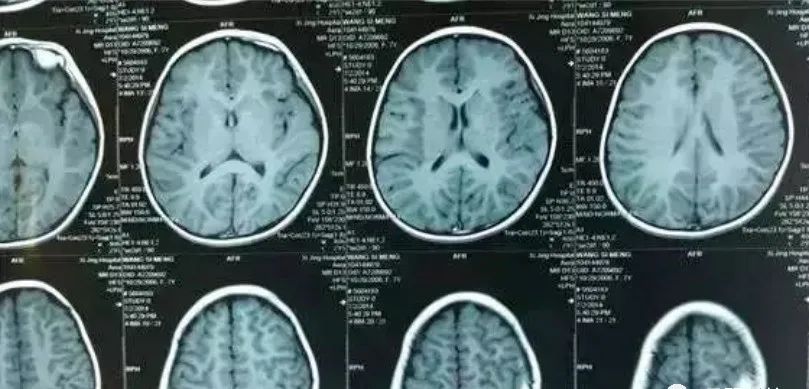

然而三个月之后,孩子的头越变越大,,并且额头突出,眼睛凹陷,这时家人带孩子到医院检查发现发现孩子的颅骨骨缝被撑开约1厘米,并且专家发现孩子的大脑两侧均有大面积的慢性硬膜下血肿,分别约100毫升,正是这不断增大的血肿将孩子的头撑大。